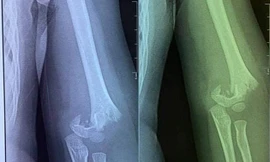

TPO - Lãnh đạo Sở GD&ĐT Hà Nội cho biết, đơn vị yêu cầu Phòng GD&ĐT và nhà trường xác minh, làm rõ sự việc trẻ bị ngã gãy tay trong Trường mầm non Vườn trẻ thơ ở quận Hai Bà Trưng.